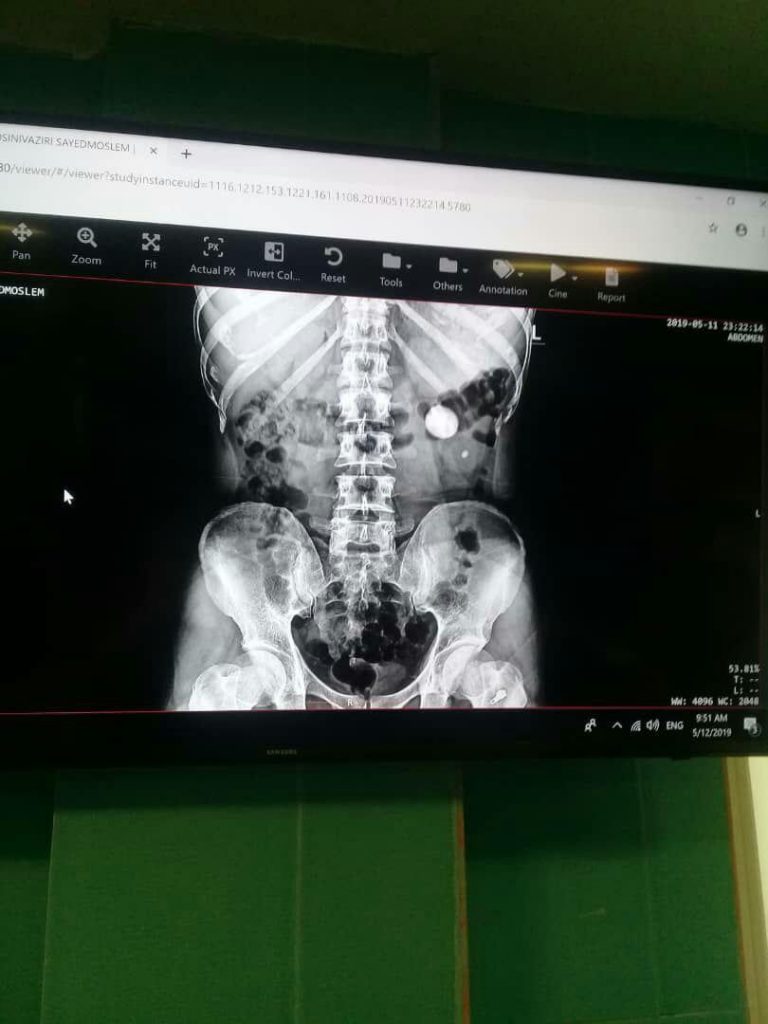

جراحی سنگ به روش بسته و PCNL

- درمان سنگ کلیه

- از بین بردن سنگ کلیه